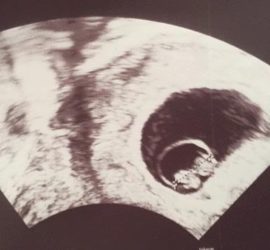

Heute ist es soweit ??Der erste Jahrestag…Sternengeburtstag…Heute vor einem Jahr war einer der glücklichsten Tage in unserem Leben!Für mich der 2. Besuch und für meinen Mann der erste Besuch bei meiner Gynäkologin in dieser Schwangerschaft.Zusammen mit unserer Tochter freuten wir […]